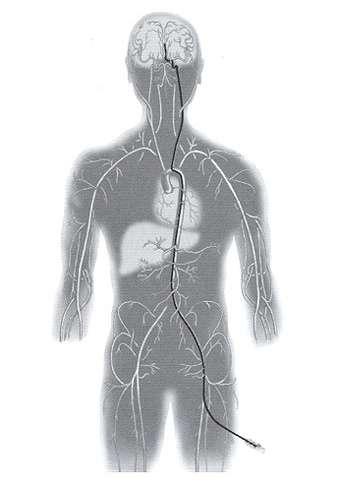

Endovascular occlusion of aneurysms includes the use of detachable coils. This is a angiographic procedure where a small soft catheter is introduced into the blood vessel from the leg artery. From there the catheter is carefully threaded up into the brain and the tip of the catheter is placed in the aneurysm (figure 6). Then through the catheter small soft coils are introduced into the aneurysm to block it completely (figure 7).